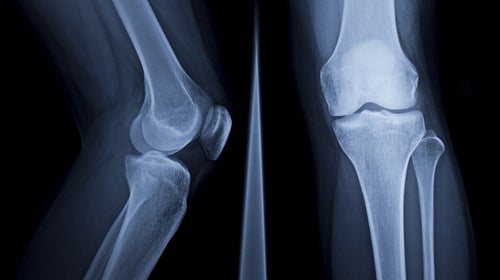

Simple strength exercises and regular aerobic training can improve bone health preemptively. (Photo: eyenigelen/iStock)

(Photo: eyenigelen/iStock)

Lead Photo: eyenigelen/iStock